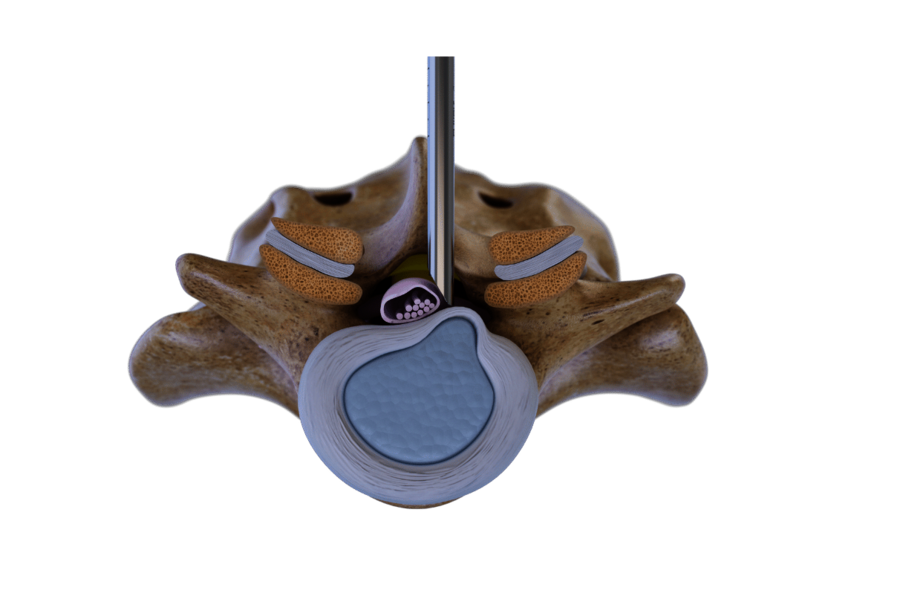

Interlaminare Technik

Der Zugang zum Wirbelsäulenkanal erfolgt durch das hintere interlaminäre Fenster. Ein Dilatator wird ohne vorherige Punktion zum Ligamentum flavum geführt. Anschließend wird die Arbeitshülse platziert, so dass der Eingriff mit einem hochauflösenden Diskoskop unter kontinuierlicher Spülung durchgeführt werden kann.

Die Komponenten des Systems sind optimiert, um das Trauma zu minimieren und die chirurgische Präzision zu erhöhen. Bandscheibenvorfälle und stenotische Knochenanteile können unter vollendoskopischer Sicht effektiv reseziert werden.